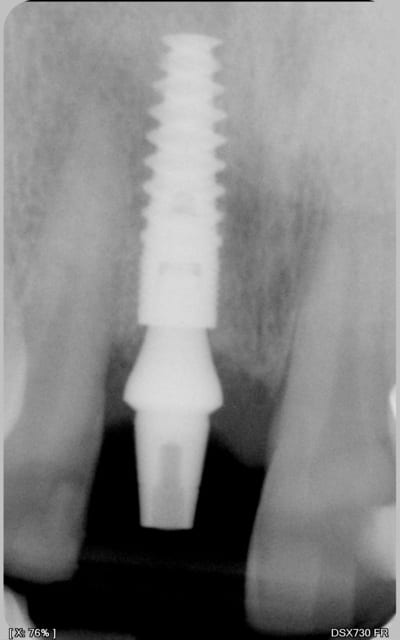

petite question: sur la photo 15, c'est la prothèse d'usage je pense, il me semble que le hiatus prothèse / pilier est important?

A pxav

Il semble effectivement qu'il y ai un hiatus important.

Je n'ai pas contrôlé l'ajustage sur le modèle car ayant travaillé avec une réplique de pilier et une chape calcinable je pensais pas qu'il puisse y avoir de défaut. A l'essayage clinique, je n'ai rien relevé à la sonde (comme quoi une sonde...) et la coiffe paraissait être à fond (occlusion et bord libre). Seule la radio de contrôle m'a révélé le problème. Comme la coiffe était déjà scellée, j'ai choisi de ne pas démonter. A surveiller....